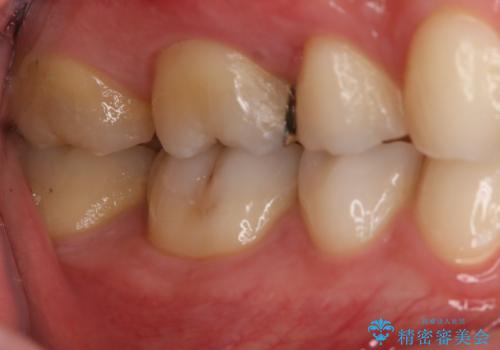

- 右上大臼歯の再治療を希望され来院された患者様です。

切削量と形状を考慮し、インレーでの治療を計画しました。

患者様がゴールドを希望されたのでゴールドインレーを選択しました。

ゴールドは金属の中でも硬すぎず破折すこともほとんどないため歯科の治療に適した材料と言われています。